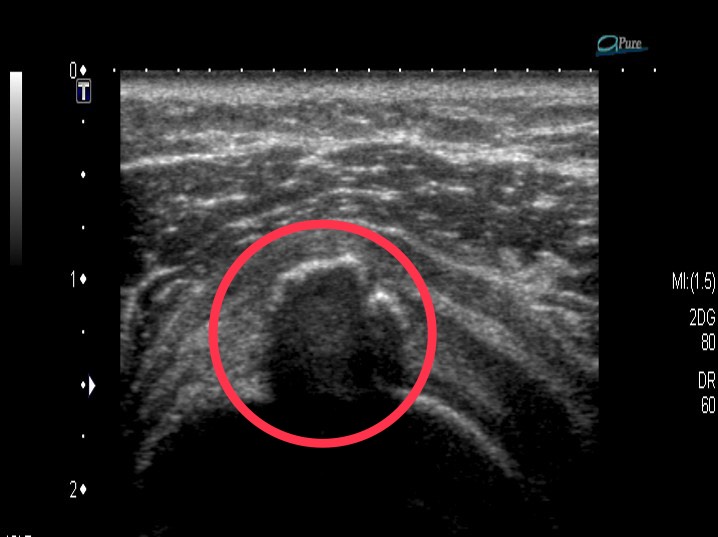

圖:圈起來為棘上肌,上方周邊亮光處即爲鈣化部位

衛生福利部臺中醫院復健科蔡逸松醫師指出,患者就醫時原以為只是睡姿不良,到藥局買了止痛藥吃未改善,就醫接受x光與超音波檢查,才發現自己右肩四條旋轉肌中負責舉手功能的棘上肌鈣化,導致無法舉手,經消炎藥、熱療一個月效果未如預期,急著返回工作崗位的她嘗試用體外震波治療,幸運治療三周後大為改善,不但可以舉手還可以輕鬆操作剪刀設計髮型;目前使用體外震波治療需自費無健保給付。